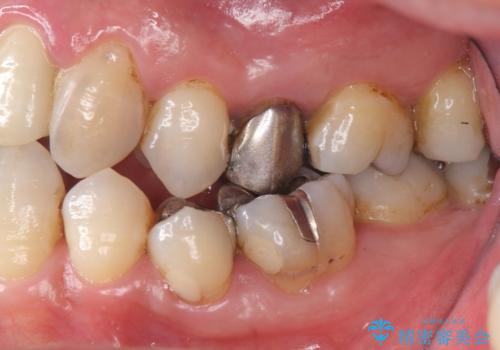

右下の奥歯も欠損しており、インプラント治療が必要な状態でした。

また、奥歯はインプラント治療を行い、矯正で下の前歯を後ろに下げるのに使用しています。

右下のインプラント治療は横浜桜木町歯科院長大元先生にお願いしています。